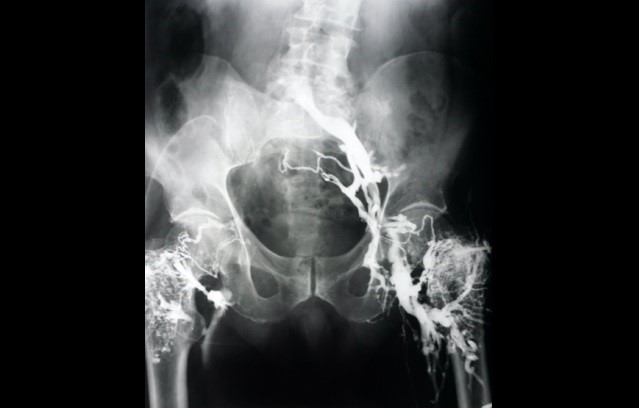

This x-ray image of blood vessels in the pelvis was captured in Edinburgh in 1970. On the right you can see blood vessels with blood flowing through them but these are missing on the left, showing that some of the vessels are blocked.

Before modern scanning techniques were developed, looking at blood vessels was a difficult task. In the early 1970s a technique called ‘intraosseous venogram’ was used - dye was injected into the bones of the upper leg, which then drained into the blood vessels of the pelvis. This dye would then show up in the veins on x-ray.